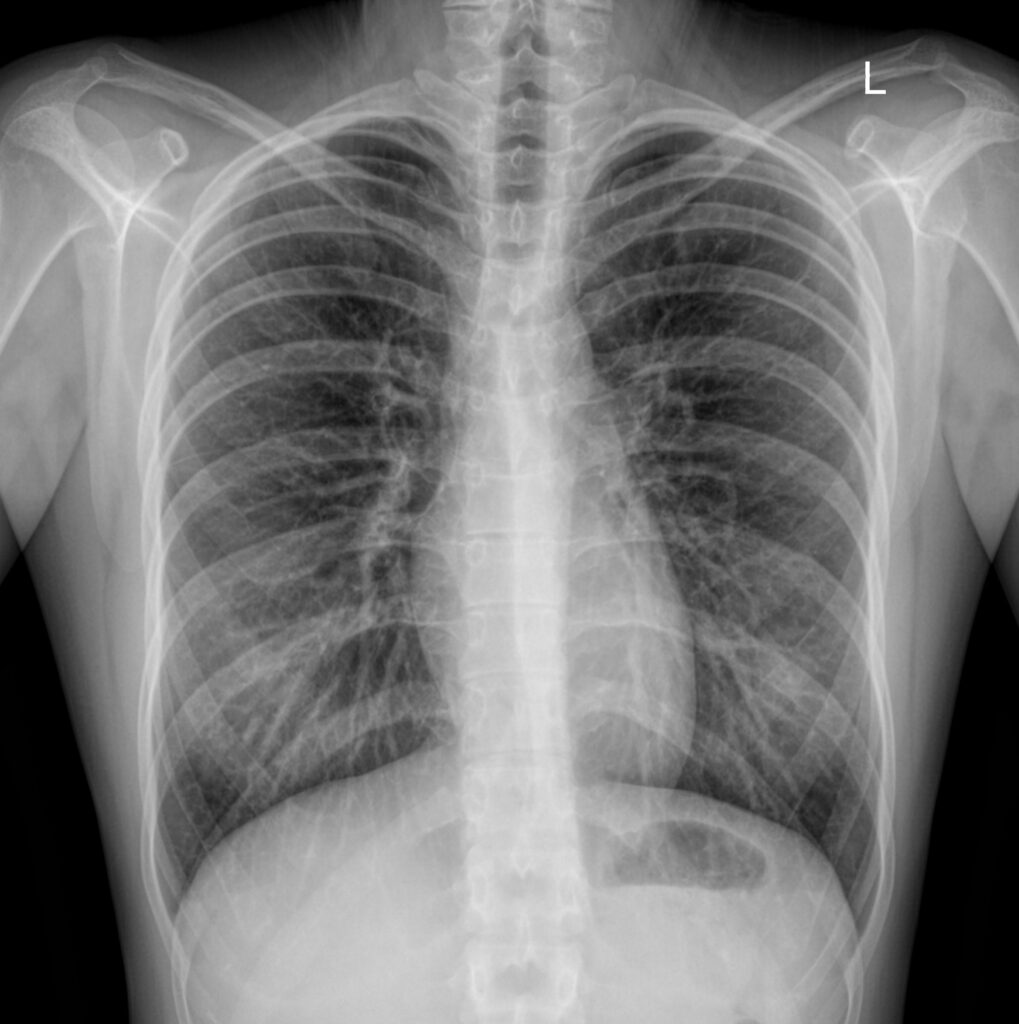

Рентген-лучи проходя сквозь структуры организма рассеиваются и частично “поглощаются”, что приводит к изменению начального потока электронов и фотонов. Так, костные структуры, состоящие по большей мере из кальция и его производных, значительно изменяют (замедляют) скорость начального потока рентген-лучей, нежели мягкие ткани. Собственно поэтому они так хорошо видны на рентгенографии.

Единицей измерения мощности лучевой нагрузки используется – миллизиверт (мЗв). При КТ исследовании лучевая нагрузка в десятки раз больше (примерно 13-20 мЗв в зависимости от исследования) наряду с обычной рентгенографией (0,08-0,11 мЗв). Правда не стоит бояться, такие риски оправданы, так как даже излучение при КТ не наносит особого вреда здоровью.